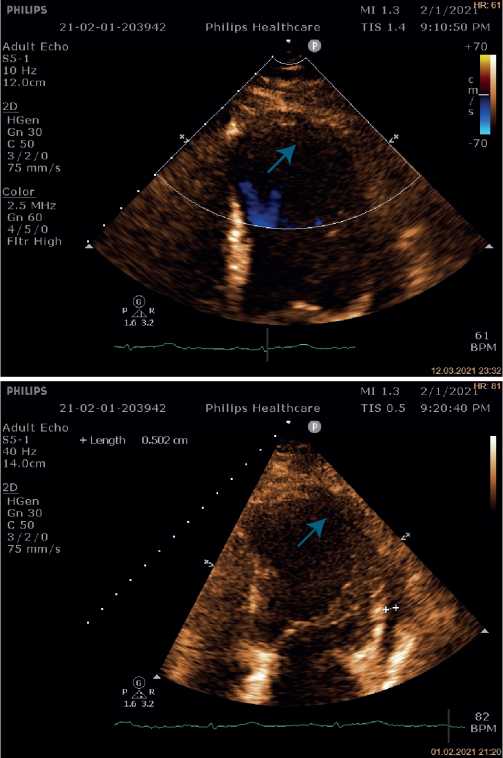

На контрольной ЭхоКГ улучшилась сократительная функция ЛЖ (табл. 1), фракция выброса ЛЖ увеличилась до 34%. Сохранялся акинез среднего и апикального сегментов межжелудочковой перегородки, передней и боковой стенок ЛЖ с захватом верхушки ЛЖ за счет формирования аневризмы ЛЖ. Сепарация листков перикарда в диастолу — 0,9 см за задней и боковой стенками ЛЖ, у верхушки — 0,6 см.

Повторное обследование проведено через 9 мес. после ИМ. По данным ЭхоКГ отмечается дальнейшее улучшение сократительной функции ЛЖ (табл. 1), фракция выброса ЛЖ достигла 43%. Отмечается акинез и выбухание среднего и апикального сегментов межжелудочковой перегородки, апикальных сегментов передней, боковой и нижней стенок ЛЖ с захватом верхушки ЛЖ, в остальных участках определяется гиперкинез. Листки перикарда уплотнены, утолщены за счет реорганизации гемоперикарда, за задней стенкой ЛЖ определяется спаечный процесс. Вдоль боковой стенки ЛЖ определяется незначительное эхонегативное пространство (сепарация в области борозды 0,67 см вдоль боковой стенки ЛЖ 0,47 см) (рис. 6). Больная стабильна, компенсирована на уровне сердечной недостаточности III функционального класса (NYHA), все рекомендации по вторичной профилактике выполняет. По-прежнему категорически отказывается от оперативного вмешательства.

Рис. 6. Трансторакальная ЭхоКГ пациентки Б.

Примечание: апикальная 2-х камерная позиция: листки перикарда уплотнены, утолщены за счет реорганизации гемоперикарда, за задней стенкой ЛЖ определяется спаечный процесс.

Сокращение: ЛЖ — левый желудочек.